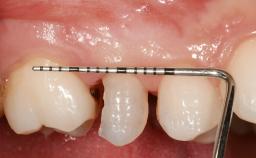

Early Placement of an Implant in a Maxillary Right Central Incisor Site

This 41-year-old female patient was referred to the clinic for the replacement of the right central incisor, since the tooth had developed a root fracture in the long axis that made extraction necessary. The healthy, non-smoking patient was first seen with the tooth still in place. A detailed Esthetic Risk Assessment was performed.The patient was worried about her dental esthetics and had high expectations for a successful treatment outcome from an esthetic point of view. The patient had a medium lip line that displayed parts of the gingiva in the anterior maxilla upon smile.